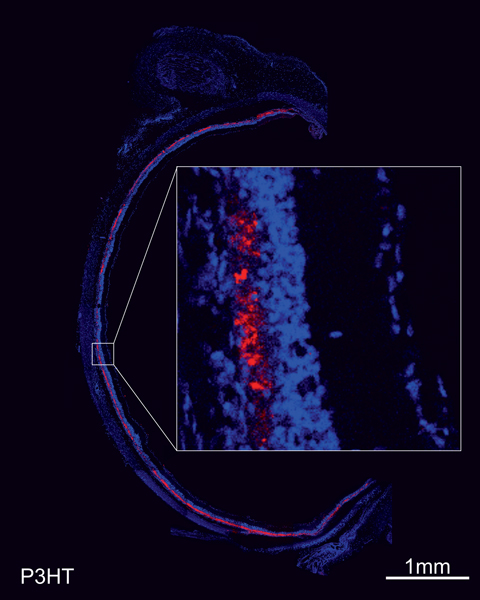

Maya-Vetencourt, J. F. et al. A fully organic retinal prosthesis restores vision in a rat model of degenerative blindness. Nat. Mater. 16 681-689 (2017).

Ghezzi, D. et al. A polymer optoelectronic interface restores light sensitivity in blind rat retinas. Nat. Photonics 7, 400–406 (2013).

Dr Serge Picaud, PhD is Research Director (INSERM, orcid.org/0000-0002-0548- 5145). He is the head of the Department of Visual Information processing at the Vision Institute. His team is investigating visual function in normal and pathological conditions to understand our vision, develop models of retinal pathology and propose new therapeutic treatments. In the last 10 years, the team has been involved in developing strategies for restoring vision from retinal implants to optogenetic therapies. These strategies are first examined on in vitro models such as retinal explants from rodent, primate or even post-mortem human retina and then validated on living rodents or non-human primates. These validations involve functional in vitro measurements from patch-clamp, multielectrode array (MEA) recording or calcium imaging and in vivo measurement like MEA recording as well as ultrafast ultrasound imaging providing greater resolution than MRI. The team has also access to phenotyping platforms on both rodents and non-human primates including the following technologies (eye fundus examination, Scanning laser ophthalmoscope (SLO), Optical coherence tomography (OCT), electroretinogram and visual evoked potential recording). Finally, restoration of vision is demonstrated by behavioural evaluations such as saccades in non-human primates. These preclinical studies have enabled the team to contribute to several products entering into clinical trials like retinal prostheses with Pixium Vision (NCT03333954) and optogenetic therapy with Gensight biologics (NCT03326336).

Bendali, A., Rousseau, L., Lissorgues, G., Scorsone, E., Djilas, M., Dégardin, J., Dubus, E., Fouquet, S., Benosman, R., Bergonzo, P., Sahel, J. A, Picaud, S. Synthetic 3D diamond-based electrodes for flexible retinal neuroprostheses: model, production and in vivo biocompatibility. Biomaterials (2015) 67: 73-83.